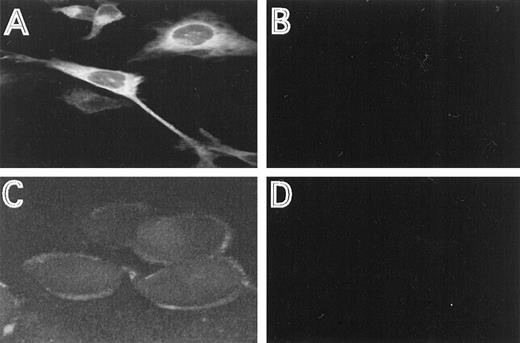

The cellular distribution of the induced HFE protein was analyzed by immunofluorescence, using HFE antisera directed against an N-terminal or C-terminal HFE peptide. In permeabilized cells, most of the staining occurred intracellular in a perinuclear location (Fig2A). This distribution is similar to the one described for the transferrin receptor.16 29 Using the antiserum directed against the N-terminal peptide, membrane staining was clearly detectable with nonpermeabilized cells, demonstrating that a distinct fraction of HFE is associated with the cell membrane (Fig2C). The specificity of the immunostaining experiments is demonstrated by the lack of fluorescence in cells repressed for HFE synthesis, under otherwise identical experimental conditions (Fig 2B and D).

Immunostaining of HFE. HtTA-HFE cells were grown on coverslips for 4 days in the absence (A,C) or presence (B,D) of 1 μg/mL doxycycline. Immunostaining was perfromed as described in the methods. Permeabilzed cells were incubated with the antiserum directed against the C-terminal peptide (A,B), unpermeabilized cells were incubated with the antiserum directed against the N-terminal peptide (C,D).

To investigate the role of HFE in cellular iron homeostasis, we studied the effects of HFE expression on transferrin iron uptake, IRP activity, and the expression of IRP target mRNAs. As a tool, we generated a stably transfected HeLa cell line that expresses HFE under control of a tet-sensitive promotor. With this cell line (HtTA-HFE), HFE synthesis can be almost completely turned off upon addition of doxycycline and be regulated by more than 2 orders of magnitude (Fig 1). The nontransfected cell line (HtTA) expresses only little HFE: (1) in Western blot experiments, no HFE-specific protein band was detected with either of the 2 peptide antisera; and (2) highly sensitive RT-PCR showed only faint HFE-specific signals after 50 amplification cycles (unpublished data, February 1998). Therefore, HFE synthesis can be strictly regulated by addition of doxycycline, making these cells a suitable model for studying HFE function. Consistent with observations in other cell systems,7,14 in the HtTA-HFE cell line most of the detectable HFE is localized intracellularly, with a distinct fraction localized at the plasma membrane (Fig 2). The staining pattern for HFE closely resembles the one obtained for the transferrin receptor (unpublished data, August 1998), in good agreement with the finding that it forms stable complexes with HFE.12 15